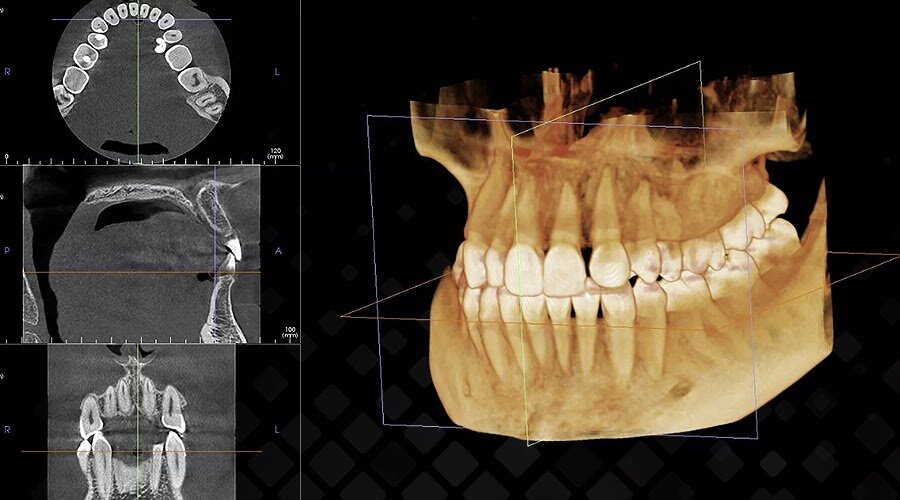

Уже сейчас трехмерные изображения с компьютерного томографа (КТ) помогают точно оценивать состояние зубов, корней и мягких тканей в полости рта – врач в мельчайших подробностях видит скрытые особенности или дефекты глубоко внутри челюстной кости.

Компьютерная томография позволяет рассмотреть строение любого элемента вашей челюстной системы буквально по слоям. Фото: Яндекс.Картинки.

Но ученые пошли дальше и подключили к анализу нейросети. Они способны программно оценивать КТ-снимки и цифровые слепки с внутриротового сканера (вместе или по-отдельности) и находить малейшие патологии с точностью 98-100%. Например, программа Diagnocat (между прочим, разработка российских стоматологов!) всего за 5 минут создает полный отчет по загруженным КТ и слепкам, и делает раскладку по каждому зубу: признаки патологий, коронки, пломбы, импланты и др.

Кроме этого появились томографы, в которые уже встроена нейросеть. Полученные снимки «прогонять» через программу не надо – анализ появляется сразу вместе со снимком.

Искусственный интеллект сверяется с обширной базой других клинических случаев (например, у Diagnocat в базе более 1 млн. размеченных зубов), анализирует найденные проблемы и помогает планировать лечение. Вся картина рассматривается нечеловечески пристально в прямом смысле. То, что может упустить человеческий глаз, программа не упускает. Так на этапе диагностики исключаются мельчайшие ошибки.